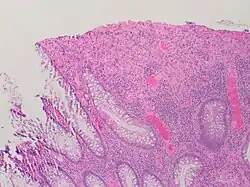

| A micrograph demonstrating cryptitis, a microscopic correlate of colitis. H&E stain. | |

An important investigation in the assessment of colitis is biopsy for histopathology. A very small piece of tissue (usually about 2mm) is removed from the bowel mucosa during endoscopy and examined under the microscope by a histopathologist. A biopsy report generally does not state the diagnosis, but should state any presence of chronic colitis, give an indication of disease activity, as well as state the presence of any epithelial damage (erosions and ulcerations).[6]

Histopathology findings generally associated with chronic colitis include:[6]

Crypt degeneration -

Crypt branching and other architectural distortions -

Paneth cell (pictured) or gastric metaplasia (only applies in the left colon and rectum)

Other findings include basal plasmacytosis and mucin depletion.[6] Histopathology findings generally associated with active colitis include:[6]

-

Neutrophilic cryptitis (neutrophils within crypt epithelium) -

Crypt abscesses (luminal neutrophilic aggregates) -

Gland destruction -

Ulceration (seen here as absence of epithelium, and granulation tissue with many fibroblasts)